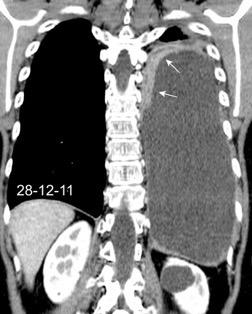

Pancreatitis. (lado izquierdo.68%)

Ortiz-Morales CM et al. Radiology of acute pancreatitis today: the Atlanta classification and the current role of imaging in its diagnosis and treatment . Radiologia (Engl Ed) . 2019

Dahnert 2017 Pancreatitis aguda